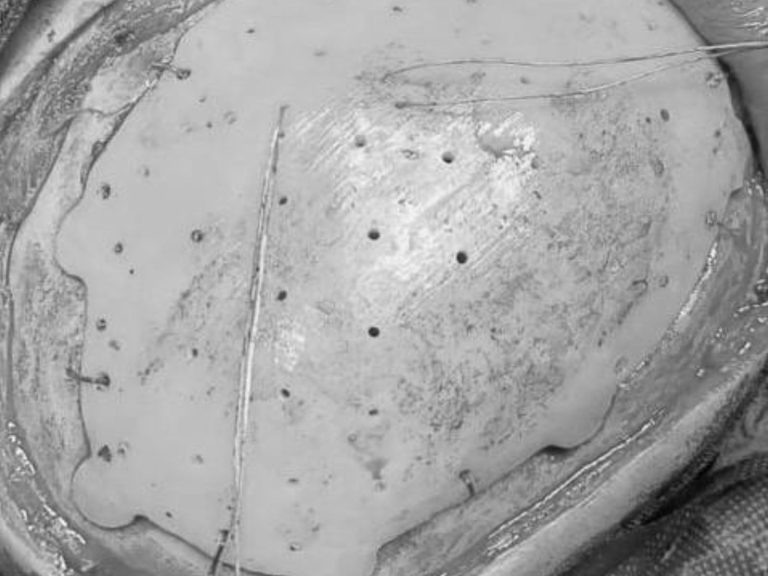

В Оренбурге хирурги восстановили юноше череп с помощью индивидуального импланта

Недостающий фрагмент костей черепа 19-летнего пациента воссоздали по снимку томографа в 3D-режиме.

Сложный послеоперационный дефект черепа в левой лобно-теменно-височной области доставлял пациенту косметический дискомфорт. Врачи Оренбургского центра хирургии и травматологии решили провести плановую операцию по восстановлению целостности черепа.

Чтобы закрыть дефект костей, для юноши заказали и выполнили индивидуальный имплант. Его изготовили по снимкам компьютерной томографии в 3-D режиме.

Операция прошла успешно и без осложнений. В настоящее время юношу уже выписали домой.

фото: Оренбургский центр хирургии и травматологии